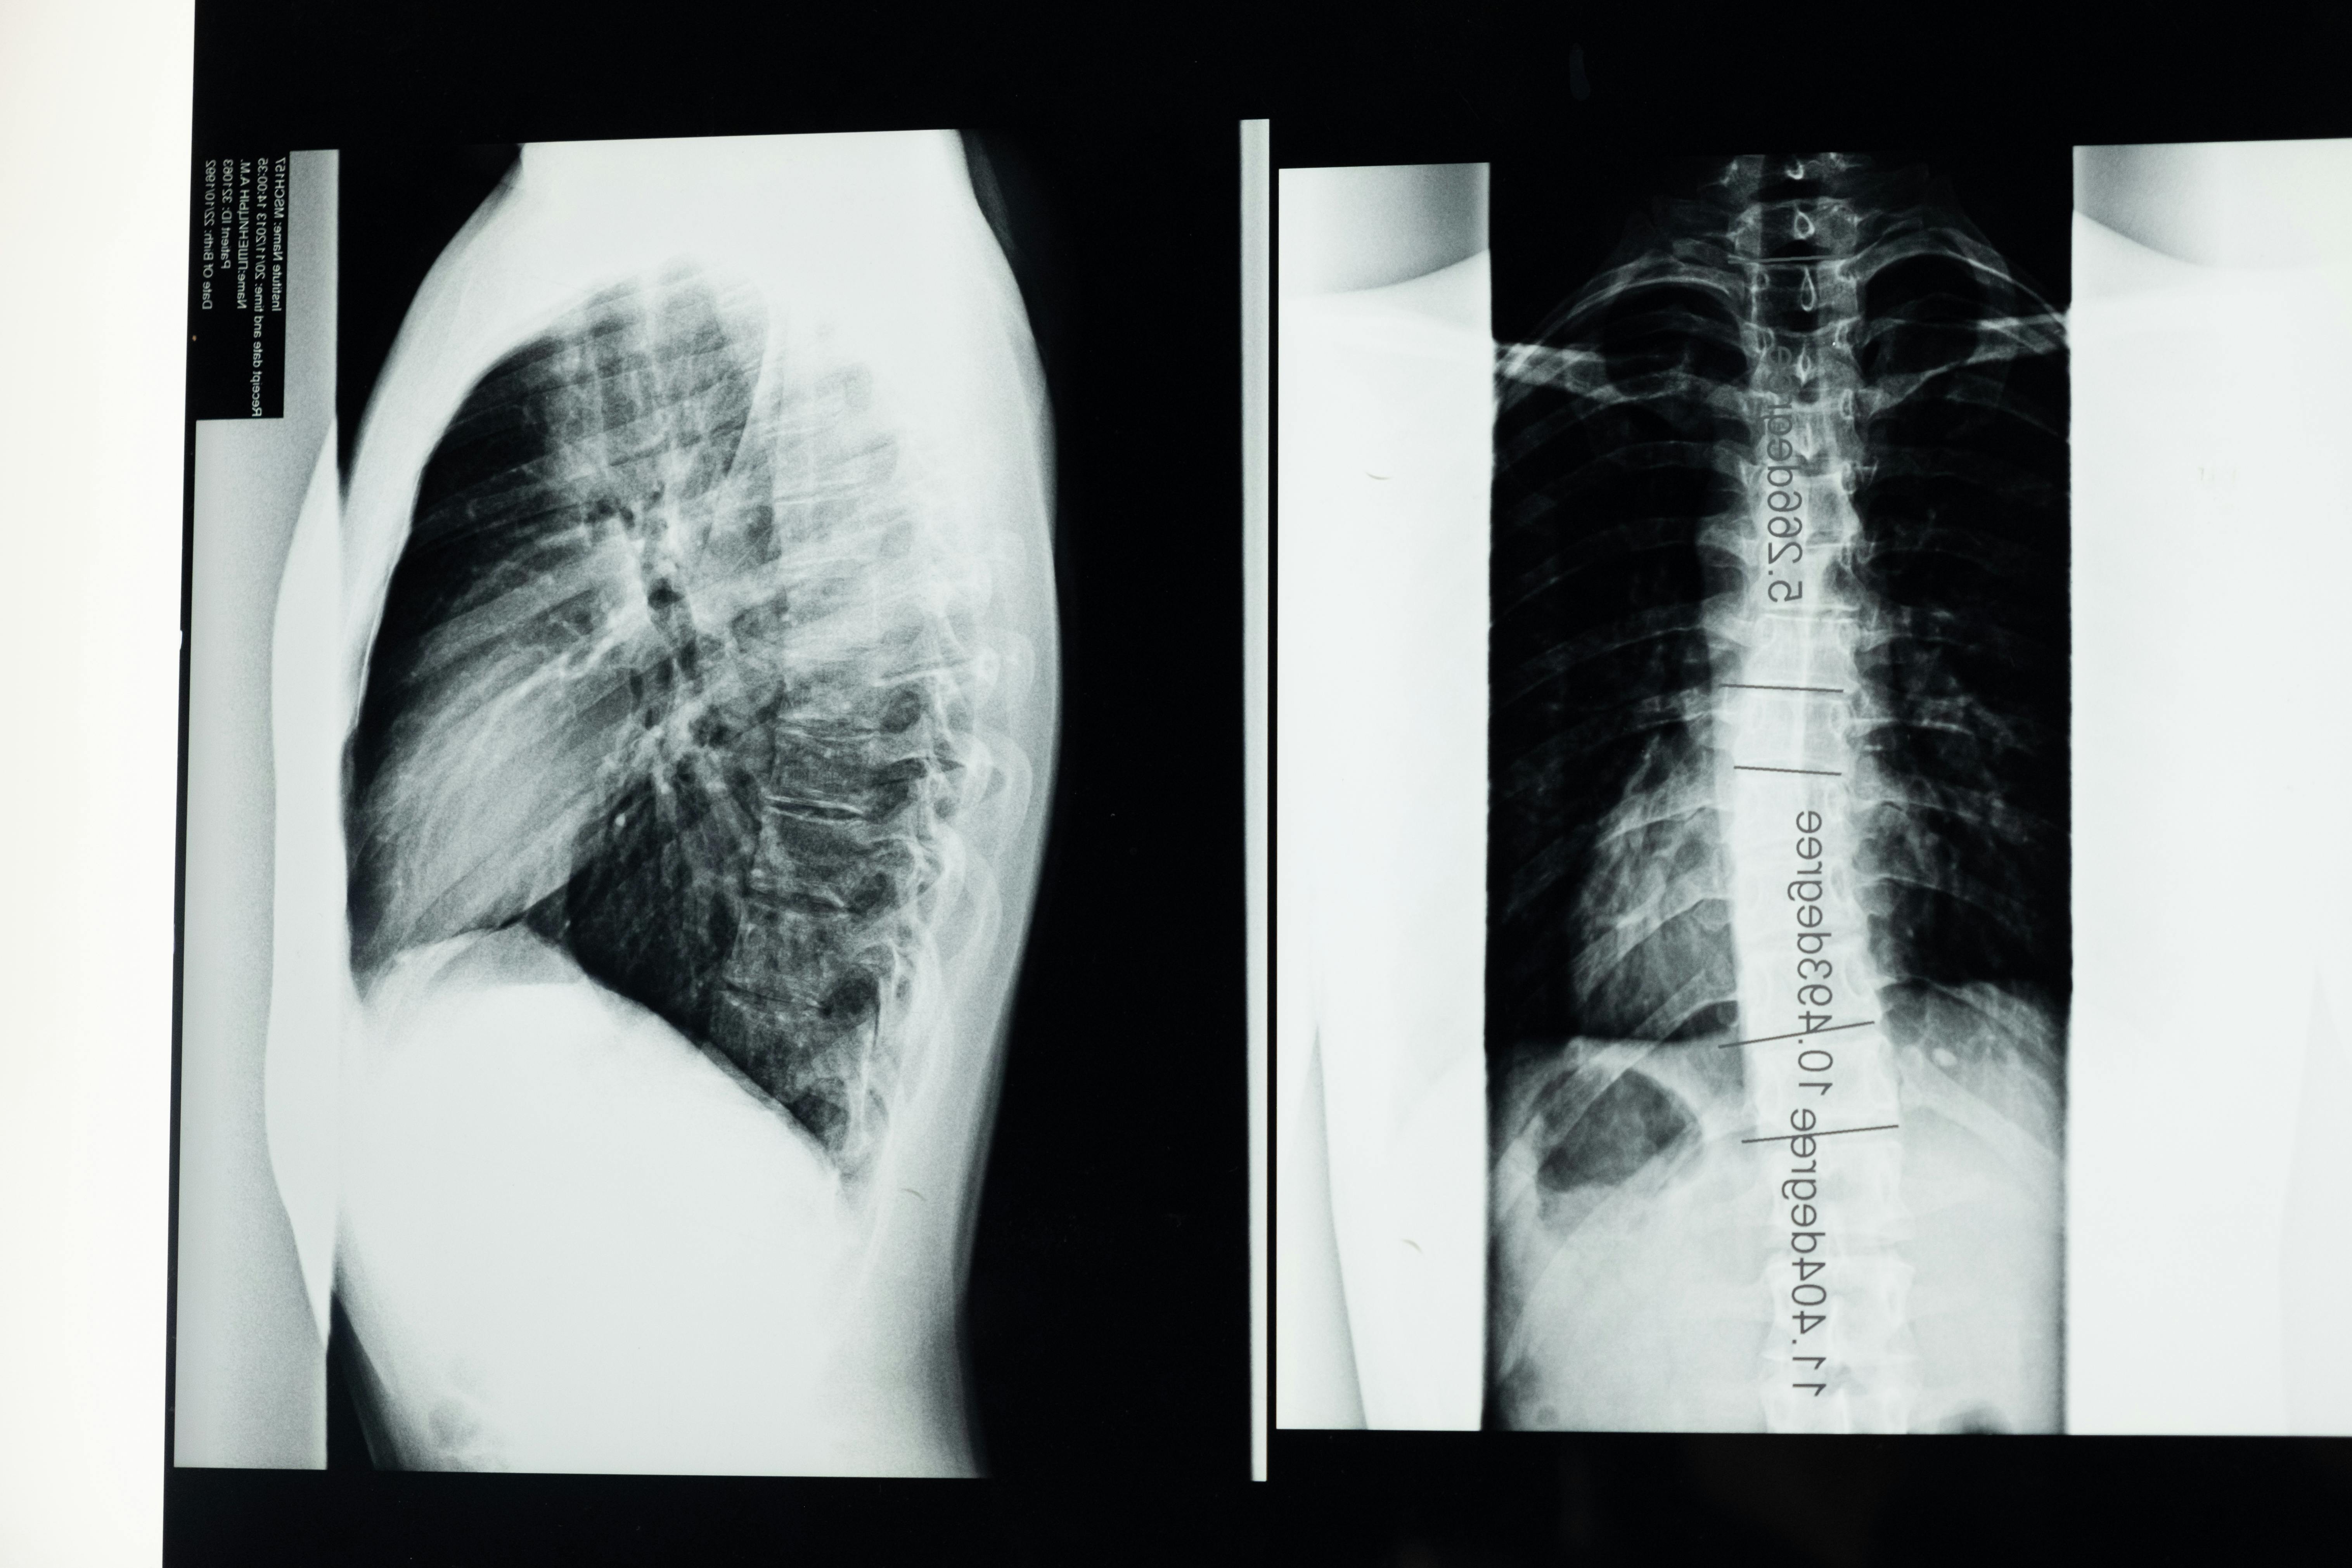

- 흉부 엑스레이: 폐결핵 등 흉부 질환 확인